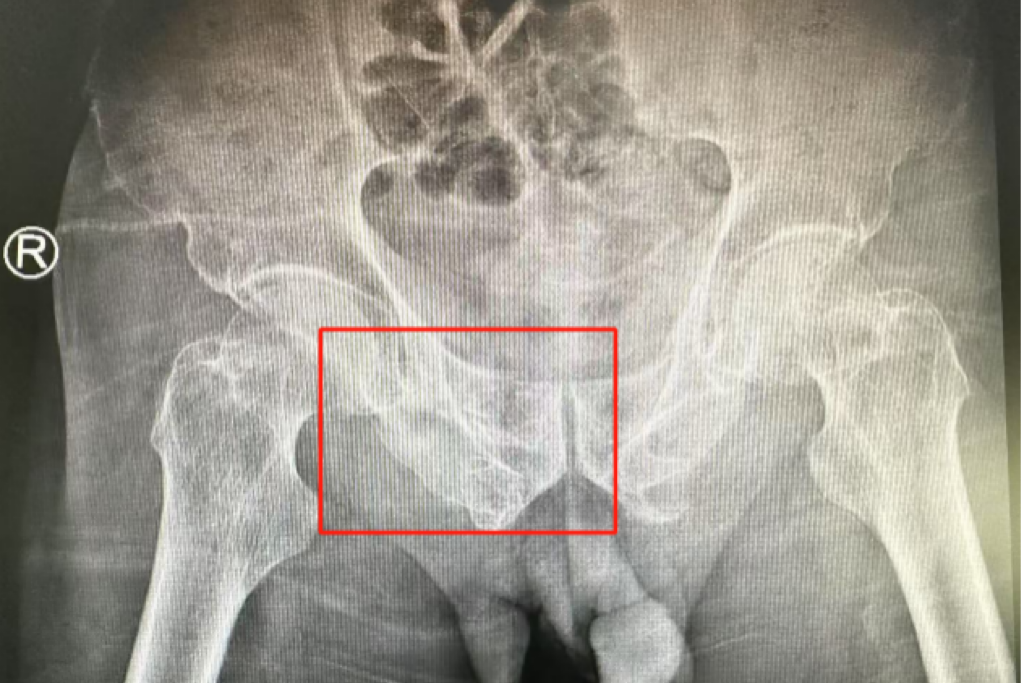

術(shù)前影像學(xué)顯示,患者的左側(cè)骶骨骨折,右側(cè)恥骨骨折、髂骨骨折,骨盆骨折分型為C型,老年脆性骨盆骨折分型為IV型,是極度不穩(wěn)定型的前環(huán)骨折和雙側(cè)后環(huán)骨折。所幸沒有明顯的骨盆出血或內(nèi)臟損傷的表現(xiàn)。

術(shù)后第二天,醫(yī)生團隊復(fù)查X片顯示螺釘植入位置非常滿意,骨折基本達(dá)到穩(wěn)定復(fù)位,同時,復(fù)查的全血細(xì)胞計數(shù)中,血紅蛋白指數(shù)為102g/L。術(shù)后第三天,在智能骨科病房護理團隊及康復(fù)師的指導(dǎo)和護理下,王大爺可以坐立在床上。術(shù)后第四天,王大爺迎來了出院日,“得虧有了這么先進的醫(yī)療技術(shù),讓我還能下地行走,謝謝你們!”

螺釘植入位置非常滿意

王大爺身體恢復(fù)良好